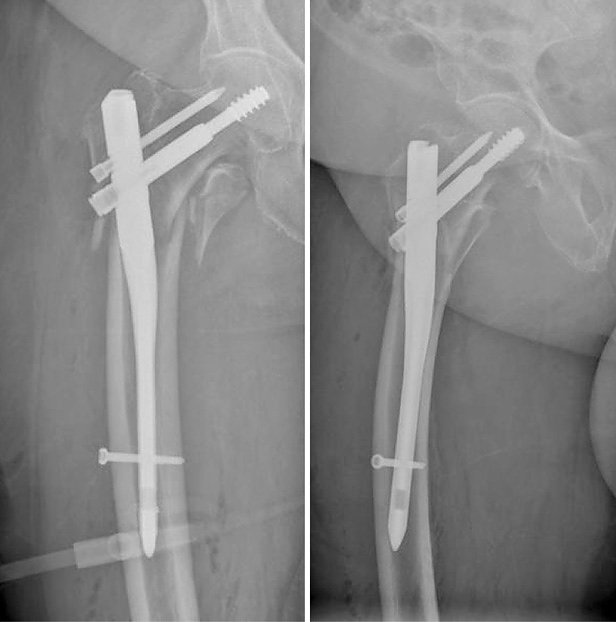

Die Erfindung der Röntgenstrahlen begründete die Radiologie. Heutzutage verwenden wir ausschließlich direkt digitale Röntgensysteme, um eine hohe Qualität der Bilddaten bei gleichzeitig niedriger Röntgendosis zu erlangen. Wir können durch eine spezielle Software auch digitale Ganzbeinaufnahmen durchführen, um so Achsfehler beispielsweise des Kniegelenks nachzuweisen. Auch eine Gesamtaufnahme der Wirbelsäule ist mit dieser sog. Stichingmethode möglich, in Nordthüringen allerdings nur in unserer Abteilung. Für die Beurteilung der Röntgenbilder, die digital gespeichert werden, wird ein automatisches Spracherkennungssystem verwandt. Ein Foschungsschwerpunkt ist die automatische Erkennung von Rundherden (also möglichen Metastasen und Tumoren) beim Röntgen der Lunge. Wir haben drei direkt digitale Röntgensysteme in der Anwendung, von Siemens, Swissray und Samsung. Für die mitunter erforderlichen Aufnahmen von Kranken auf der intensivstation werden zwei fahrbare Röntgeneinheiten genutzt, von Shimadzu und Siemens.